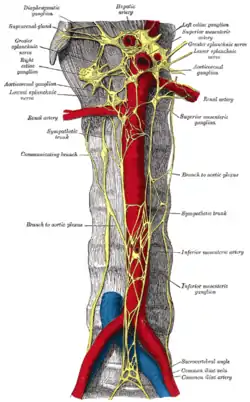

Abdominal portion of the sympathetic trunk, with the celiac and hypogastric plexuses. (Greater splanchnic and lowest splanchnic labeled at upper left. Greater splanchnic and lesser splanchnic labeled at upper right.) | |